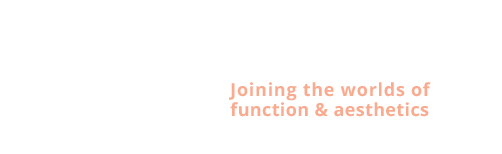

Cyriel: Slaap apnea

Diagnose van het gezicht

- Te kleine onderkaak (Overbeet)

- Te kleine bovenkaak

- Slaap apnea

Esthetische chirurgie

- Liposuctie